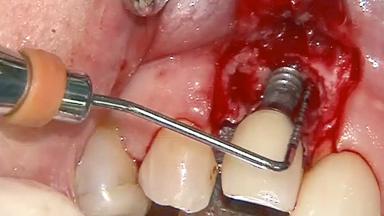

Peripheral Giant-cell Granuloma Associated with Peri-implant Tissues

Giant-cell granulomas (GCG) of the jaws are benign reactive lesions of unknown etiology, unrelated to giant-cell tumors (osteoclastomas), which are defined as benign but locally destructive and aggressive neoplasms (Jundt and coworkers 2005). Depending on their localization at the initial diagnosis, GCG are dived into central (CGCG) and peripheral (PGCG) types. CGCGs occur within the jawbones and appear as unilocular or multilocular radiolucent lesions. The incidence in the general population is very low. They are more commonly found in the mandible, mainly in children and young adults—patients are generally younger than 30 years—and have a greater incidence in females (Heithersay and coworkers 2002). The clinical behavior of CGCGs varies from slowly growing asymptomatic swellings to aggressive lesions that may result in pain, cortical perforation of the affected jaw site, and root resorption (de Lange and coworkers 2007).